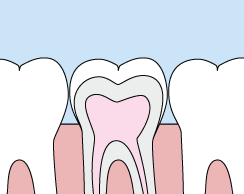

Crowns are a cosmetic restoration used to improve your tooth’s shape or to strengthen a tooth. Crowns are most often used for teeth that are broken, worn, or have portions destroyed by tooth decay.

A crown is a "cap" cemented onto an existing tooth that fully covers the portion of your tooth above the gum line. In effect, the crown becomes your tooth’s new outer surface. Crowns can be made of porcelain, metal, or both. Porcelain crowns are most often preferred because they mimic the translucency of natural teeth and are very strong.

Crowns or onlays (partial crowns) are needed when there is insufficient tooth strength remaining to hold a filling. Unlike fillings, which apply the restorative material directly into your mouth, a crown is fabricated away from your mouth. Your crown is created in a lab from your unique tooth impression, which allows a dental laboratory technician to examine all aspects of your bite and jaw movements. Your crown is then sculpted just for you so that your bite and jaw movements function normally once the crown is placed.